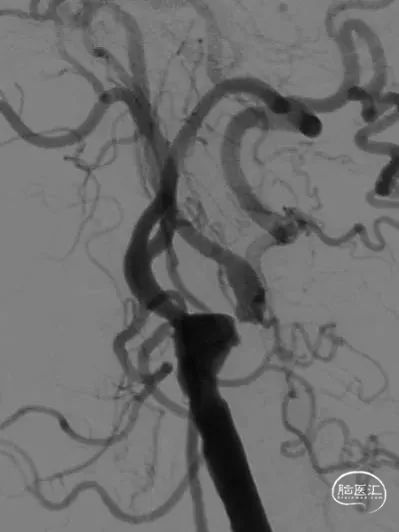

8F导引导管到位后复查造影,在路图指引下将PT微导丝小心通过病变,旋转以确定真腔,后采用2-20mm小球囊预扩张,后采用交换技术置入远端保护装置,再次造影确认无误后根据测量结果使用4-20mm球囊扩张成形,之后植入Precise7-30mm支架,准确定位后释放,术后复查造影见远端血流改善,支架位置良好,管腔轻度残余狭窄,查体同术前,结束手术。

支架术后即刻DSA显示支架充盈良好,残余轻度狭窄。

术后即刻DSA提示颅内动脉充盈改善,无明显血管影像缺失。

患者规律药物治疗,3月后入院复查DSA提示左侧颈动脉支架位置良好,残余狭窄较前减轻,支架与管腔贴合良好。